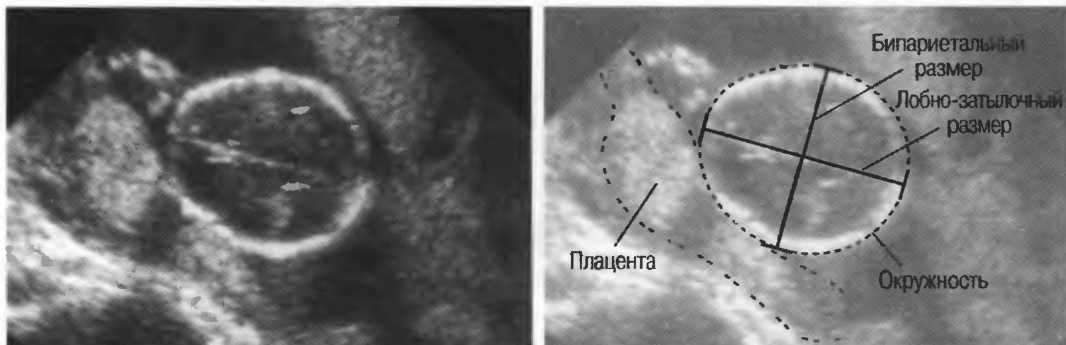

На эхограммах рис. 13 представлены различные варианты регулировки чувствительности и усиления по глубине.

Рис. 13г. Головка плода. Слева: общая чувствительность слишком высока. Справа: общая чувствительность определена правильно, однако она слишком высока для точного измерения бипариетального диаметра.

Рис. 13д. Общая чувствительность слишком низка для исследования внутренней зхоструктуры, но достаточна для точного измерения бипариетального диаметра.

Рис.13е. Слева: плохая визуализация в результате слишком высокого усиления передних отделов; сравните нечеткое изображение передней части головки с достаточно четким изображением задних отделов (сравните рис. 13ги 13д;. Справа: регулировка по глубине была изменена; теперь определяется слишком низкое усиление близких структур и слишком высокое усиление глубокорасположенных структур.